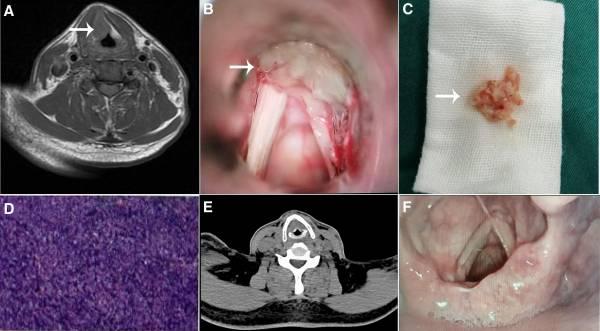

图1 喉部非霍奇金淋巴瘤的治疗过程。(A)术前颈部MRI结果,肿物如箭头所示。(B)术中发现的肿物如箭头所示。(C)切除肿物的术中标本。(D)术后病理结果。(E)术后随访颈部CT显示甲状腺区域无肿物。(F)术后两个月,随访喉镜检查未发现复发

2024年8月31日,患者在全身麻醉下接受了声门上肿物切除。术中发现证实,肿瘤起源于右侧喉室,部分累及前连合。采用高频电刀进行切除,观察到灰白色肿物。对肿瘤进行组织病理学检查(图1B和C)。术后病理证实了非霍奇金B细胞淋巴瘤(侵袭性)的诊断,免疫组织化学证实了弥漫性大B细胞淋巴瘤的诊断(非生发中心表型)(图1D)。

手术后,2024年9月11日的术后18F脱氧葡萄糖正电子发射断层扫描显示,咽喉区没有异常,也没有其他肿瘤的证据。颈部、纵隔和腋窝区域的小淋巴结显示葡萄糖代谢低,与炎症或反应性淋巴结病一致。随访的颈部计算机断层扫描(CT)显示声门肿胀和声门间隙变窄(图1E),而胃肠内镜没有显示任何远处转移。患者被转诊到血液科进行骨髓抽吸术,结果显示红系增生,但没有其他异常。由于经济困难,他选择了利妥昔单抗和来那度胺化疗。术后2个月的随访电子喉镜检查显示没有复发(图1F),患者仍在接受持续的随访。